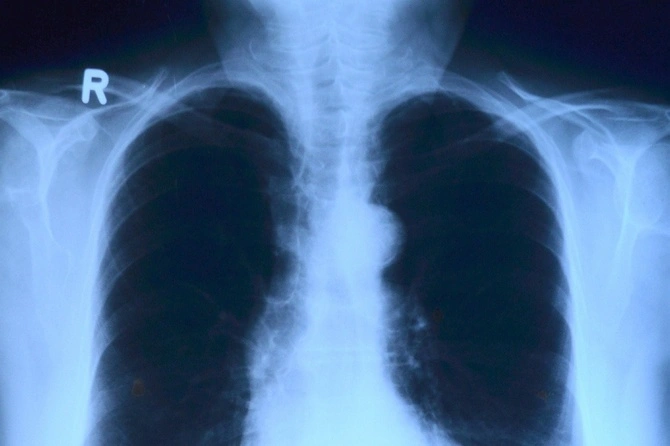

Врач-эндокринолог, заведующая центром ГБУЗ «Городская клиническая больница №29 им. Н.Э. Баумана» Мария Свиридова предупредила, что рентген, а также хирургические вмешательства, проведенные в области шеи, могут нарушить функции щитовидой железы.

«Основные патологии связаны со снижением функций щитовидной железы. Когда это бывает? Это бывает после операций на щитовидной железе. Какие-то вмешательства в области шеи, в основном, конечно, на щитовидной железе, стараются сделать органосберегающими. Тем не менее, достаточно часто после операций на щитовидной железе возникает так называемый гипотериоз и пациенту требуется лечение», — сказала она радиостанции «Говорит Москва».

Также на работе щитовидной железы пагубно сказывается воздействие радиации.

«Вторая причина — например, по какому-то другому заболеванию человек вынужден был подвергаться облучению в области шеи. Радиационному, рентгеновскому, бывают такие ситуации. Тоже часто не работает щитовидная железа. Часто она не восстанавливается после таких облучений, потому что возникает воспаление. В исходе воспаления вместо пораженной ткани возникает соединительная ткань, то есть появляются рубцы и, когда щитовидная железа сильно поражена в результате лечения, ее работы недостаточно», — подытожила она.